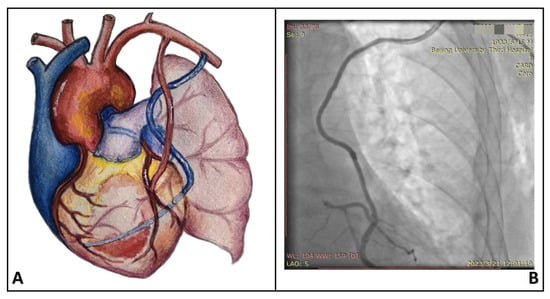

MICS-CABG was performed using an off-pump technique through a minimally invasive thoracotomy (4–6 cm incision) placed in the left fourth or fifth intercostal space between the midclavicular and anterior axillary lines. All procedures were conducted under direct vision. Details on the surgical techniques have been described previously [8]. In the Aorta (AOR) group, a side-biting clamp was applied to the aortic wall, followed by an aortic punch and proximal anastomosis of the saphenous vein graft (SVG). In the Axillary (AXA) group, a 3 cm transverse incision was made below the left clavicle at the junction of the middle and lateral thirds. The left axillary artery was dissected and exposed, and the proximal end of the SVG was anastomosed to the axillary artery using 6–0 Prolene sutures. The SVG was then passed through the first intercostal space into the thoracic cavity, routed along the chest wall to the level of the aortic arch, and further routed along the left cardiac border toward the target coronary vessels for sequential distal anastomoses. Detailed procedural aspects of MICS-CABG and the inclusion and exclusion criteria relative to conventional CABG or MICS-CABG have been reported previously and are therefore not reiterated here [9]. The configuration of the SVG and its corresponding postoperative angiographic appearance in the AXA group are presented in Figure 2.

Figure 2.

Schematic illustration of the saphenous vein graft course with proximal anastomosis to the left axillary artery (A), as well as the corresponding postoperative graft angiography (B).